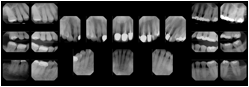

OO.1.2 Ophthalmology

1. A patient in rural Canada visits a general ophthalmologist and is found to have diabetic macular edema. The general ophthalmologist would like to discuss the case with a retina specialist before performing laser surgery. A fluorescein angiogram is done with multiple retinal images taken in a timed series after an intravenous injection. The images along with a Structured Display are shared via a Health Information Exchange with a retina specialist in Calgary, who opens them using his Ophthalmology EMR software and consults via phone with the general ophthalmologist. Both physicians view the images in the same layout so the retina specialist can provide accurate guidance for treating the patient.

2. A patient in rural Iowa visits his primary care physician for management of diabetes. Three non-mydriatic (patient's eyes are not dilated) photographs are taken of the back of each eye, and forwarded electronically along with a Structured Display to an ophthalmologist in Iowa City. The ophthalmologist reads the photos in an agreed upon layout so there is no mistake about what portion of which eye is being viewed. The ophthalmologist is able to tell the primary care physician that his patient does not need to come to Iowa City for face to face ophthalmologic care, but that there is a particular view of the left eye that should be photographed again in 6 months.